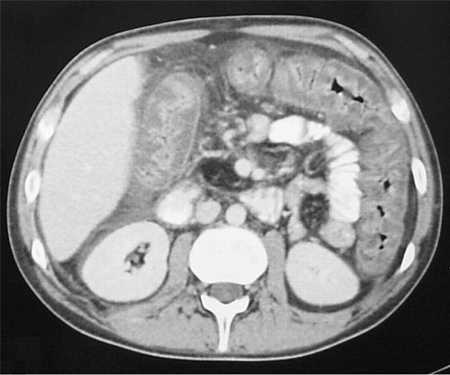

CT scan of the abdomen showing gross thickening of the large bowel wall and obliteration of the lumen

Yates B, Murphy CM, et al. Pseudomembranous colitis in four patients with cystic fibrosis following lung transplantation. BMJ Case reports. 2009; doi: 10.1136/bcr.11.2008.1218